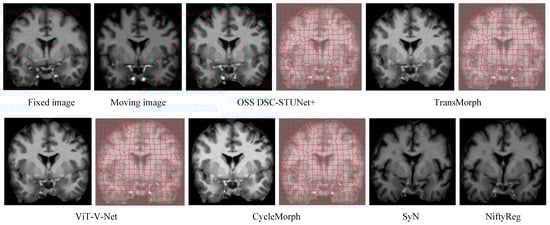

From Table 1, it can be observed that the proposed model achieved a Dice score on the IXI dataset that was 7.0% higher than CycleMorph, 6.6% higher than VoxelMorph, 16.3% higher than NiftyReg, 16.2% higher than SyN, 4.8% higher than ViT-V-Net, and 2.3% higher than TransMorph. From Table 2, the model’s Dice score on the OASIS dataset was 5.3% higher than CycleMorph, 4.8% higher than VoxelMorph, 9% higher than NiftyReg, 7.5% higher than SyN, 4.2% higher than ViT-V-Net, and 1.8% higher than TransMorph. From Table 3, on the LPBA40 dataset, the proposed model’s Dice score was 7% higher than CycleMorph, 5.9% higher than VoxelMorph, 1.1% higher than NiftyReg, 1.7% higher than SyN, 5.4% higher than ViT-V-Net, and 2.6% higher than TransMorph. Figure 7 and Figure 8 present the registration results of the different methods on the IXI dataset and OASIS dataset, respectively. From Figure 7 and Figure 8, it can be observed that the proposed method not only exceled in global accuracy compared to the conventional registration methods but also better preserved the details in the images.

In Figure 7, the feature segmentation map for the IXI dataset shows that the model demonstrated a higher level of attention to complex and irregular edges than models like TransMorph. The advantage of OSS DSC-STUNet+ over the other methods lay in its ability to extract both global and local features, which can be validated through the registration images and their corresponding feature segmentation maps.

Figure 8. Registration results and segmented images of different methods on the OASIS dataset (z = 124).

Jimaging 11 00054 g008